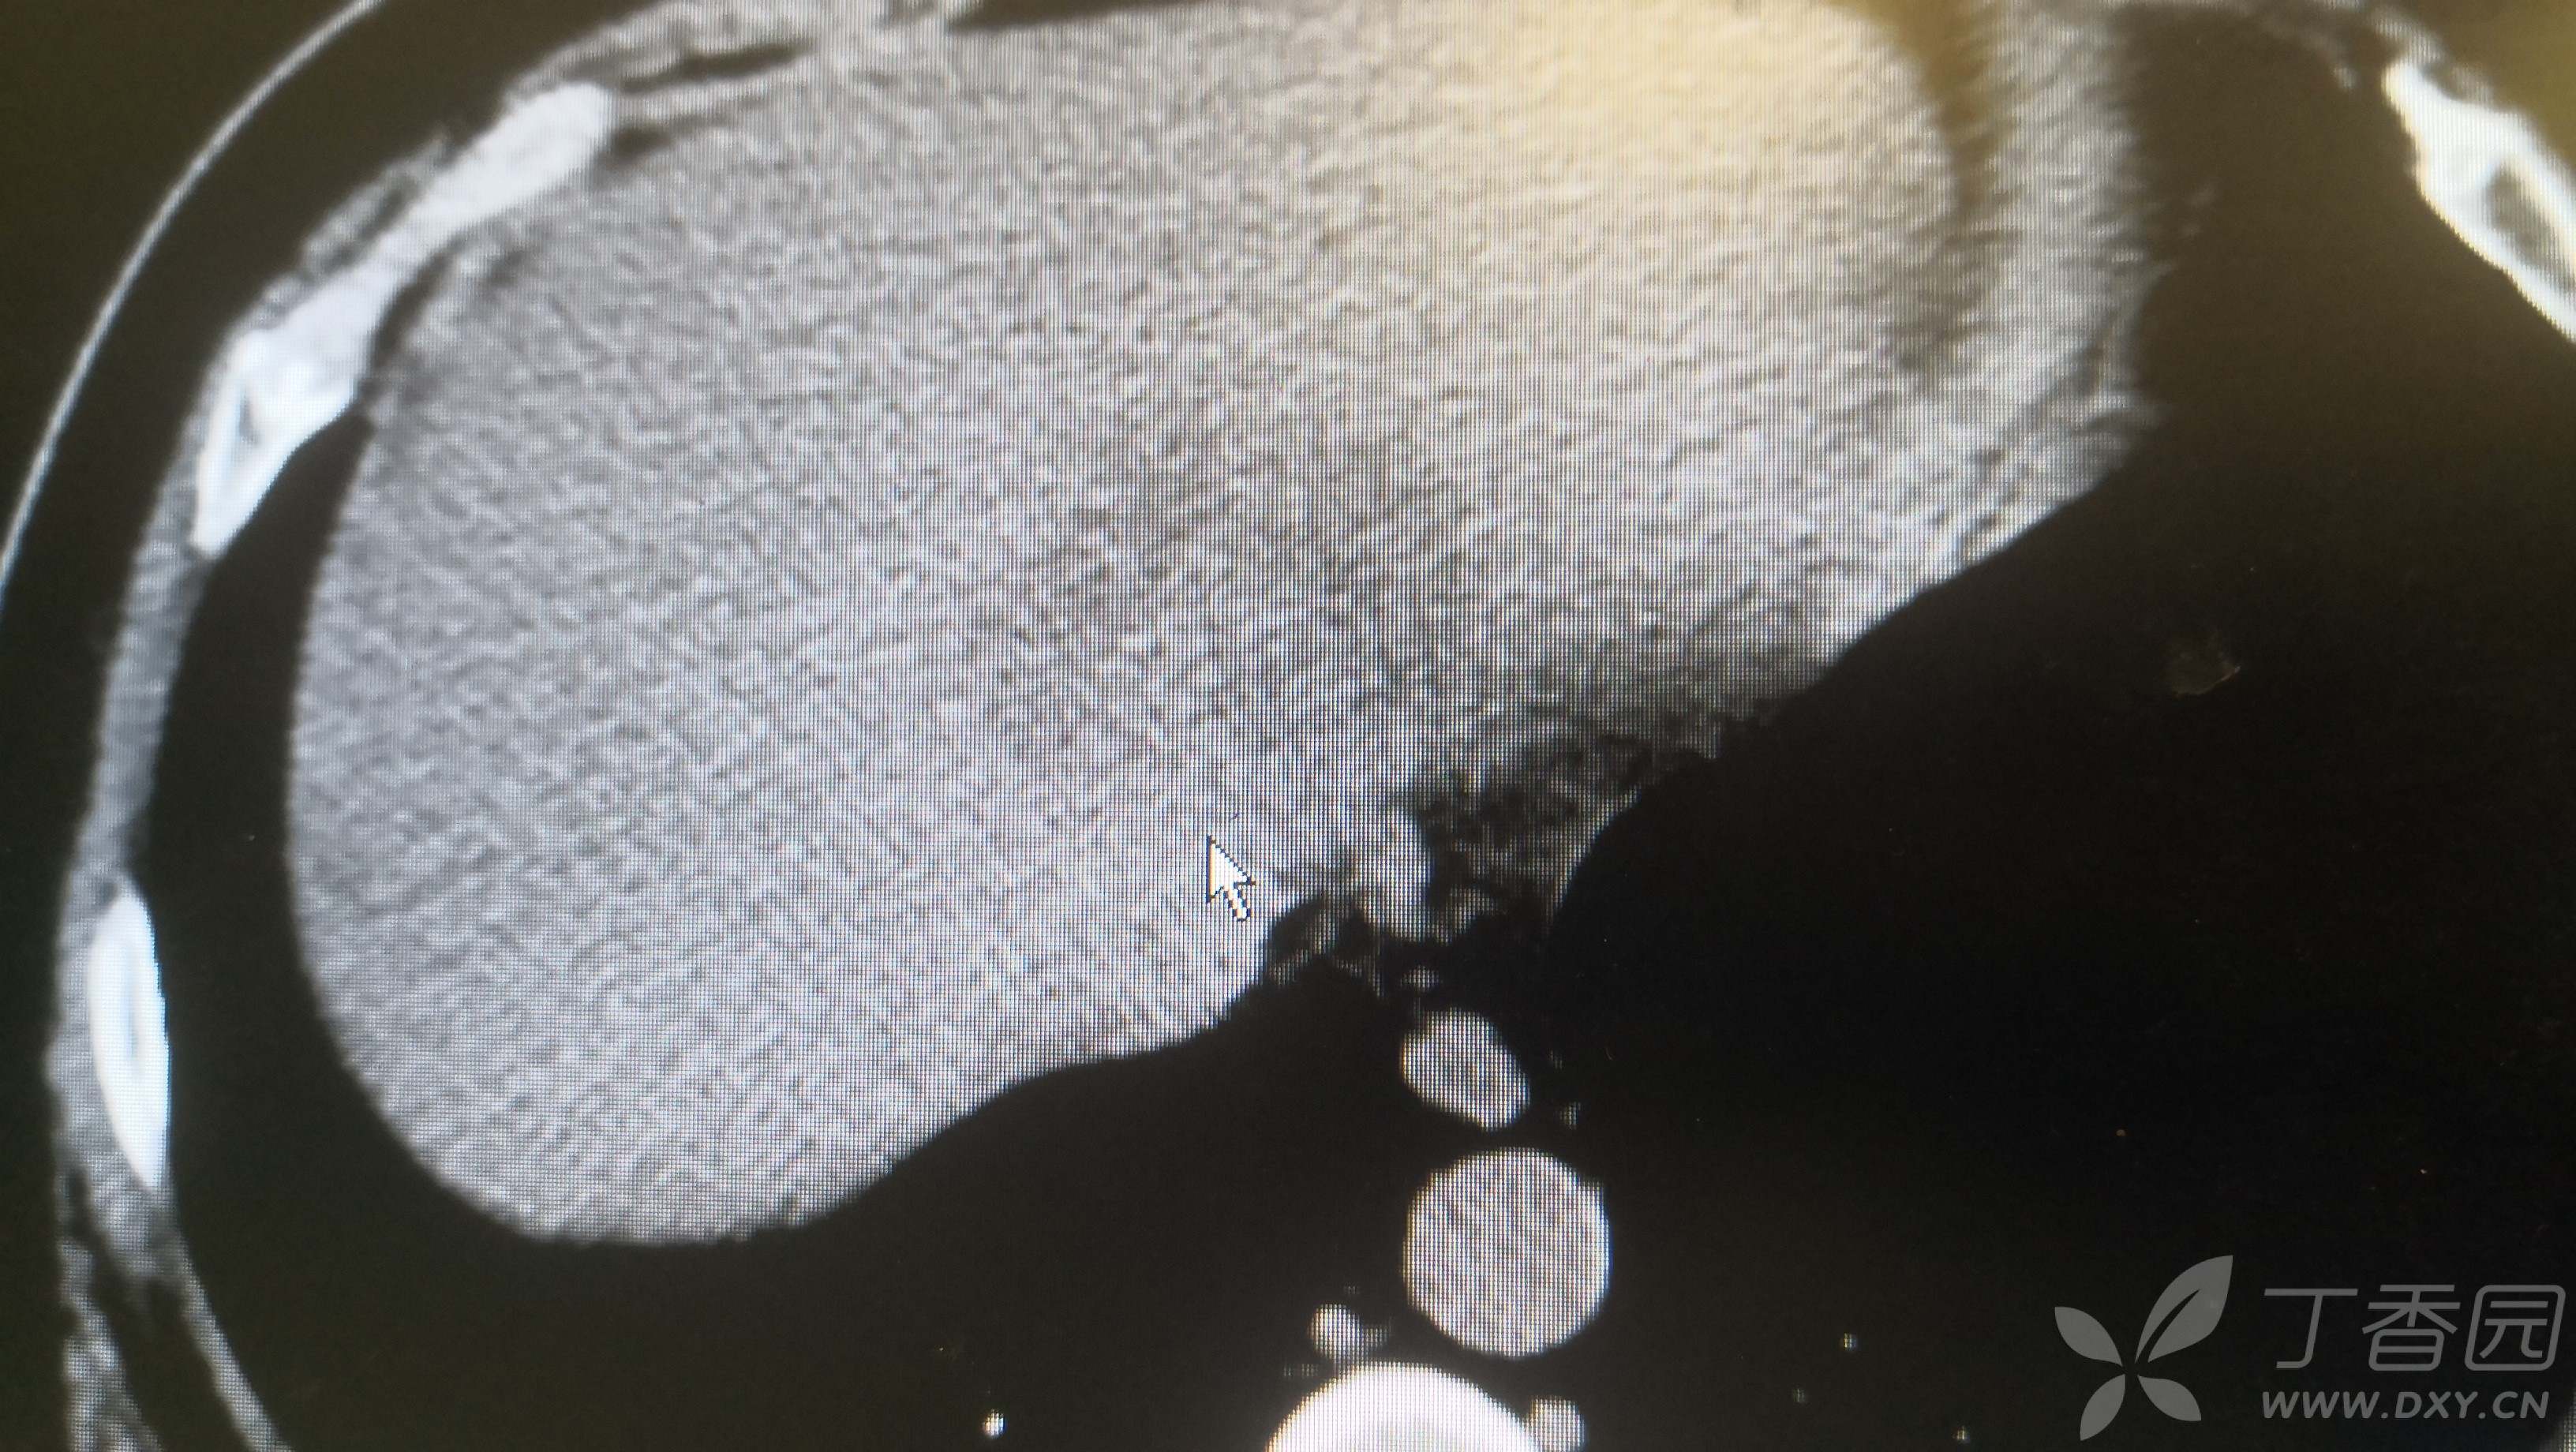

腹部CT如下: